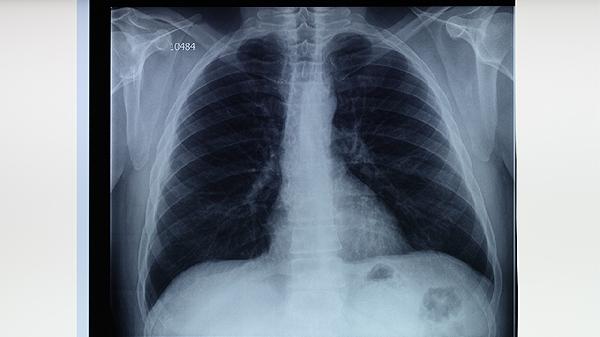

肺結(jié)核病的治療方法主要有生活干預(yù)、藥物治療、手術(shù)治療等方式。肺結(jié)核病是由結(jié)核分枝桿菌感染引起的慢性傳染病,主要通過呼吸道傳播,患者需積極配合醫(yī)生治療。

肺結(jié)核病患者需定期復(fù)查胸部X線、痰涂片等檢查,監(jiān)測治療效果。治療期間如出現(xiàn)藥物不良反應(yīng)如肝功能異常、視力下降等情況,應(yīng)及時就醫(yī)調(diào)整用藥方案?;颊咝枳龊脗€人防護,咳嗽、打噴嚏時用紙巾遮住口鼻,痰液需消毒處理,避免傳染他人。堅持規(guī)范治療,絕大多數(shù)肺結(jié)核病患者可完全康復(fù)。